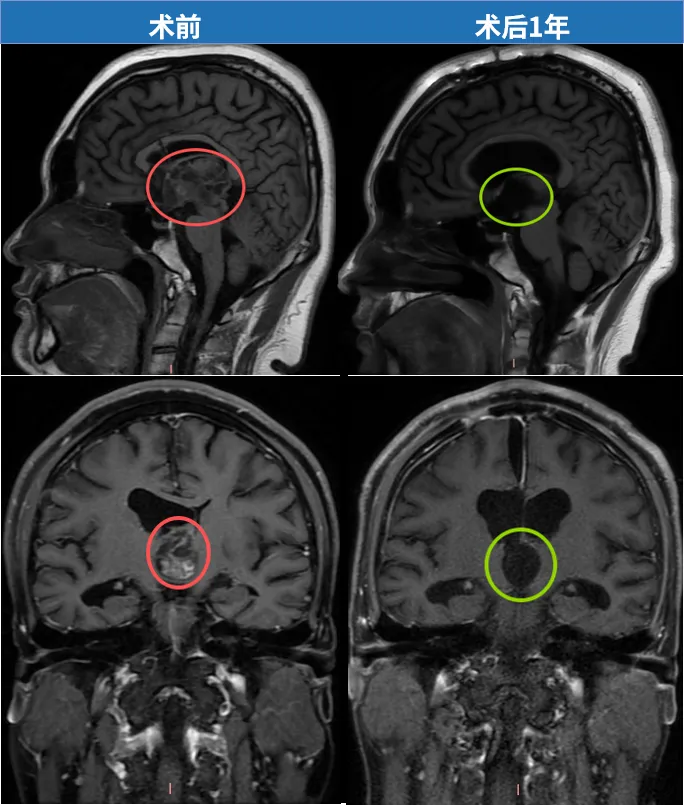

这条治疗道路充满挑战。从最初发现脑肿瘤并选择保守观察开始,经历症状反复波动、全家人的担忧焦虑、以及多种治疗尝试——包括中医药治疗。直至2025年8月12日,一台关键手术改变整体病情。位于大脑核心区域第三脑室的巨大肿瘤,由INC巴特朗菲教授主刀,联合北京天坛医院医疗团队,通过精密稳健的手术操作,实现高危脑瘤的"完全切除"。术后病理诊断确认为毛细胞星形细胞瘤,全切手术意味着良好预后,也标志着飞宇迈出摆脱疾病阴霾的重要一步。

术后近5个月随访复查时,巴特朗菲教授表示:"针对这例毛细胞型星形细胞瘤,我们实现了肿瘤全切除。重要脑部结构均得到完整保留,特别是穹隆等关键部位,因此患者具有良好恢复机会。正如之前所述,患者年龄较轻,但恢复仍需时间。不过,儿童的恢复潜力非常可观。"

随后他们尝试中医药治疗,可惜效果不佳。现实终究严峻:飞宇在成长,肿瘤也在增大。眼科检查出现复视现象,视力显著下降、视野缺损——MRI检查显示,40毫米的巨大肿瘤已占据第三脑室,正悄然侵蚀少年的未来。

术前MRI检查结果

"今年复查显示肿瘤继续增大,不能再等待。"这次,他们毫无犹豫。恰逢巴特朗菲教授来华交流,从7月31日复查到8月12日手术,仅间隔十余天。"实际上我们从开始就认定要选择最佳治疗方案。这是脑部手术,我们必须给他最好的医疗条件。"

这个40×25×31毫米的巨大肿瘤完全占据第三脑室,并从室间孔向下压迫中脑结构,使手术面临多重挑战。首先,手术路径深长且狭窄,需要在切开胼胝体、分离脉络膜裂后,在有限操作空间内精准切除肿瘤,对手术稳定性要求极高。其次,肿瘤导致关键脉络膜裂发生扭曲、变薄,与周围深部静脉系统和丘脑粘连紧密,分离过程中极易引发出血或梗死。再者,肿瘤本身血供丰富且质地坚韧类似橡皮,与第三脑室壁、丘脑、深部血管紧密粘连,只能分块切除或借助超声吸引器(CUSA),强行牵拉容易导致出血或损伤周围组织。